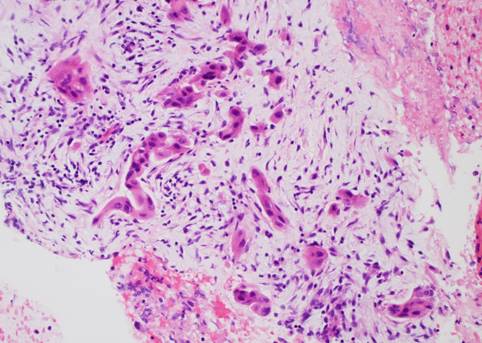

*Pancreatic adenocarcinoma on an EUS-guided biopsy of a pancreatic head mass.